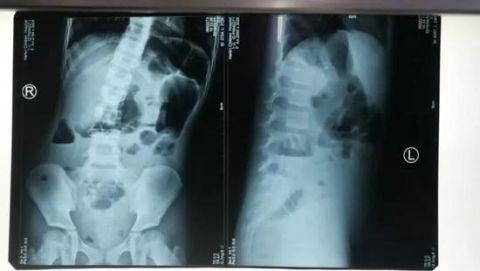

几天前,琳琳因腹痛厉害被送到了医院,经过影像科检查,医生发现女孩腹内有一个畸胎瘤并发生扭转,要立即手术。

王主任说,在肿瘤的影像上显示:

畸胎瘤中还有骨组织,应为孩子的双胞胎弟弟或妹妹,因胚胎发育异常而包在孩子的体内,最终形成了畸胎瘤,有些畸胎瘤内甚至还能有牙齿、毛发等。畸胎瘤可存在于人体内的各个部位,大多数为良性。